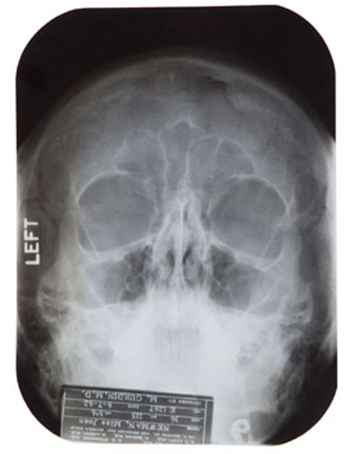

기록에는 50년대에 그녀는 자신의 턱에 불만을 가지고 있으며 턱에 연골 임플란트 시술을 받은 것으로 돼 있다. 또 이기록에는 1957년에는 뉴욕에서 정상 위치가 아닌 이소성 임신을 한 적이 있었으며 1962년 여름 한 밤중에 넘어져 코뼈와 이가 부어오른 사실도 담고 있다.